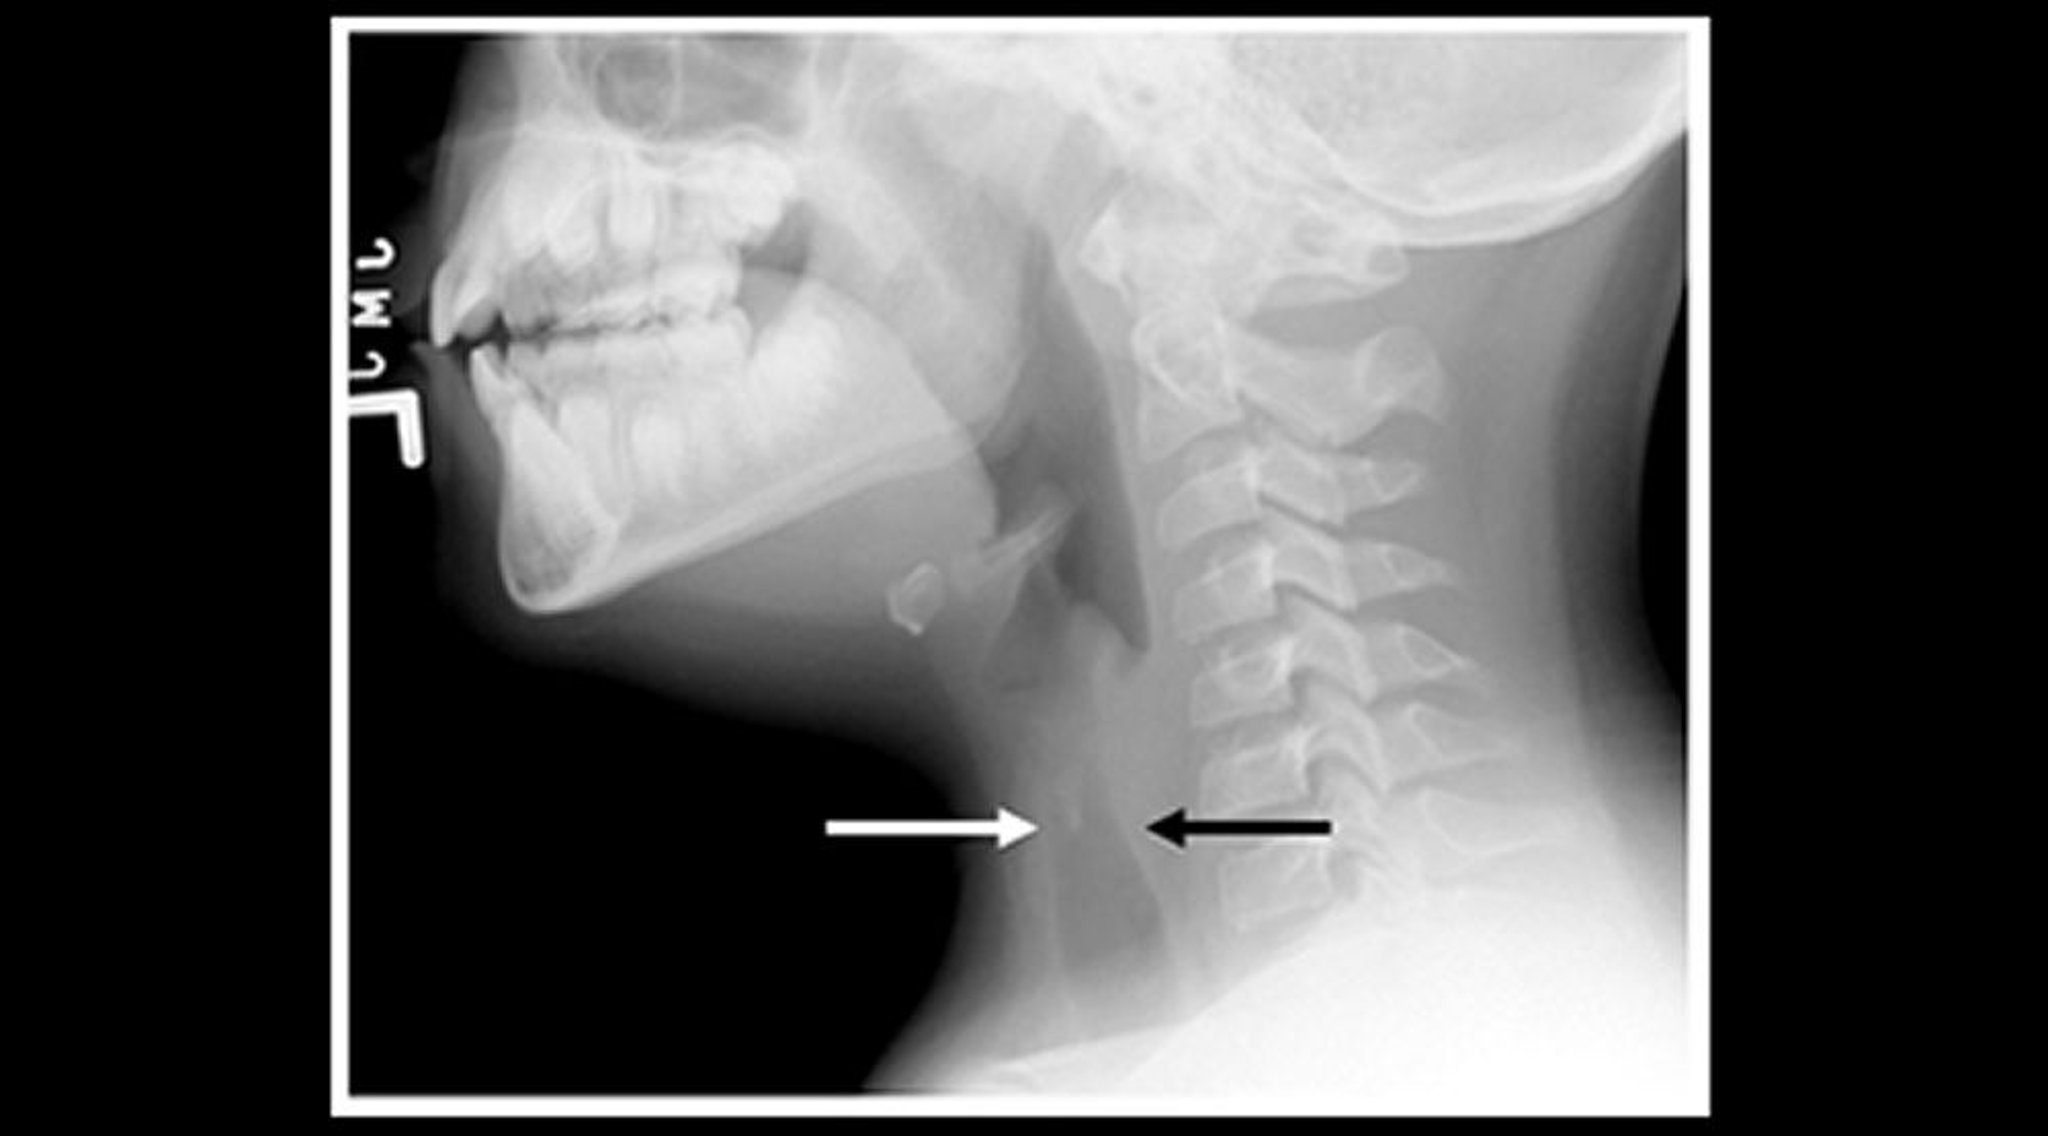

Röntgenbild eines Kindes mit Krupp (Sagittalansicht)

Röntgenaufnahmen der Halsweichteile eines Kindes mit Krupp zeigen eine Einengung des subglottischen trachealen Luftschattens (Pfeile) und eine Erweiterung der pharyngealen Luftzwischenräume.